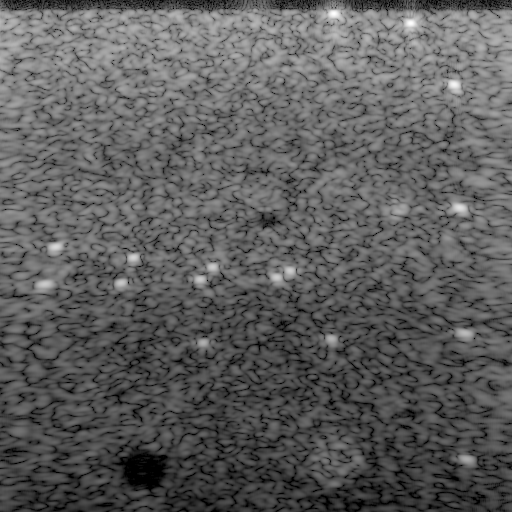

2.11.1F-number (1) 4.56.1Frequency f𝑓f (MHz) Refer to caption-151515 -101010 -555 00 555 101010 151515 101010151515202020252525303030353535404040Lateral position x𝑥x (mm)Axial position z𝑧z (mm)-707070 -606060 -505050 -404040 -303030 -202020 -101010 00 dB/dividedecibelabsent\mathrm{dB}\text{/}Refer to caption351 µm/times351dividemicrometerabsent351\text{\,}\mathrm{\SIUnitSymbolMicro m}\text{/} Transmit focal lengthMagnified region (inset image)

Figure 2: Image of the multi-tissue phantom for the full apertures. These apertures achieved the best lateral resolution at the expense of grating lobe artifacts and image nonuniformity. The image shows the absolute voxel values for three transmit focal lengths (cyan triangles).

The usage of the full apertures, as shown in Fig. 2, resulted in grating lobe artifacts close to the linear array and nonuniform image quality. The grating lobe artifacts resembled moiré patterns (i.e., patterns of alternating dark and bright areas) that differred from the usual speckle pattern [3]. The wires close to the transmit foci had the smallest lateral FWHM. These widths increased significantly away from the transmit foci because the DOFs were too small. These small DOFs, as stated in Table I, also resulted in suboptimal contrast of the large anechoic region.

2.11.1F-number (1) 4.56.1Frequency f𝑓f (MHz) FixedProposedF-number in transmit focusing FixedProposedF-number in receive focusing Refer to caption-151515 -101010 -555 00 555 101010 151515 101010151515202020252525303030353535404040(a)Refer to caption743 µm/times743dividemicrometerabsent743\text{\,}\mathrm{\SIUnitSymbolMicro m}\text{/} Refer to caption-151515 -101010 -555 00 555 101010 151515 101010151515202020252525303030353535404040(b)Refer to caption613 µm/times613dividemicrometerabsent613\text{\,}\mathrm{\SIUnitSymbolMicro m}\text{/} Refer to caption-151515 -101010 -555 00 555 101010 151515 101010151515202020252525303030353535404040Lateral position x𝑥x (mm)Axial position z𝑧z (mm)(c)-707070 -353535 00 dB/dividedecibelabsent\mathrm{dB}\text{/}Refer to caption705 µm/times705dividemicrometerabsent705\text{\,}\mathrm{\SIUnitSymbolMicro m}\text{/} Refer to caption-151515 -101010 -555 00 555 101010 151515 101010151515202020252525303030353535404040(d)Refer to caption591 µm/times591dividemicrometerabsent591\text{\,}\mathrm{\SIUnitSymbolMicro m}\text{/} Transmit focal lengthMagnified region (inset image)

Figure 3: Images of the multi-tissue phantom for dynamic apertures. All F-numbers, in comparison to the full apertures (see Fig. 2), eliminated grating lobe artifacts and improved both image uniformity and contrast. The proposed F-numbers, however, improved the lateral resolution by up to 24 %/times24dividepercentabsent24\text{\,}\mathrm{\char 37\relax}\text{/} with respect to the fixed F-numbers. The images show the absolute voxel values for three transmit focal lengths (cyan triangles) and all combinations of transmit (rows) and receive F-numbers (columns). The transmit F-numbers are the fixed F-number F3.1𝐹3.1F\approx 3.1 (top row) and the proposed F-number (2) with DOF13 mm/DOFtimes13dividemillimeterabsent\text{DOF}\approx$13\text{\,}\mathrm{mm}\text{/}$ (bottom row). The receive F-numbers are the fixed F-number F=1.5𝐹1.5F=1.5 (left column) and the proposed F-number (3) with χ0=60 °/subscript𝜒0times60dividedegreeabsent\chi_{0}=$60\text{\,}\mathrm{\SIUnitSymbolDegree}\text{/}$, Fub=1.5subscript𝐹ub1.5F_{\text{ub}}=1.5, and δ=10 °/𝛿times10dividedegreeabsent\delta=$10\text{\,}\mathrm{\SIUnitSymbolDegree}\text{/}$ (right column). The axes in all images are equal.

The usage of dynamic apertures, as shown in Fig. 3, eliminated grating lobe artifacts and improved both image uniformity and contrast. The interquartile range (IQR) of the lateral FWHM and the gCNR of the large anechoic region, according to Table I, improved by up to 14.1 %/times14.1dividepercentabsent14.1\text{\,}\mathrm{\char 37\relax}\text{/} and 8.3 %/times8.3dividepercentabsent8.3\text{\,}\mathrm{\char 37\relax}\text{/}, respectively. The exact lateral FWHM of the wires, however, depended strongly on the F-numbers. The fixed F-numbers, as shown in Fig. 3(a), increased the lateral FWHM of all wires in comparison to the full apertures (see Fig. 2). This increase, as shown in Fig. 3(c), was mitigated by the proposed transmit F-number (2). The proposed receive F-number (3), as shown in Fig. 3(b), improved this mitigation because the dynamic receive focusing did not require a large DOF. The combination of the proposed F-numbers (2) and (3), as shown in Fig. 3(d), achieved the best lateral FWHM of all four investigated combinations. The lateral FWHM of the wire in the magnified region, for example, reduced by 20.5 %/times20.5dividepercentabsent20.5\text{\,}\mathrm{\char 37\relax}\text{/} in comparison to the fixed F-numbers. The highest reduction of 24 %/times24dividepercentabsent24\text{\,}\mathrm{\char 37\relax}\text{/} was achieved for the wire in the lower right corner. The median lateral FWHM of all wires, according to Table I, reduced by 15.9 %/times15.9dividepercentabsent15.9\text{\,}\mathrm{\char 37\relax}\text{/}.